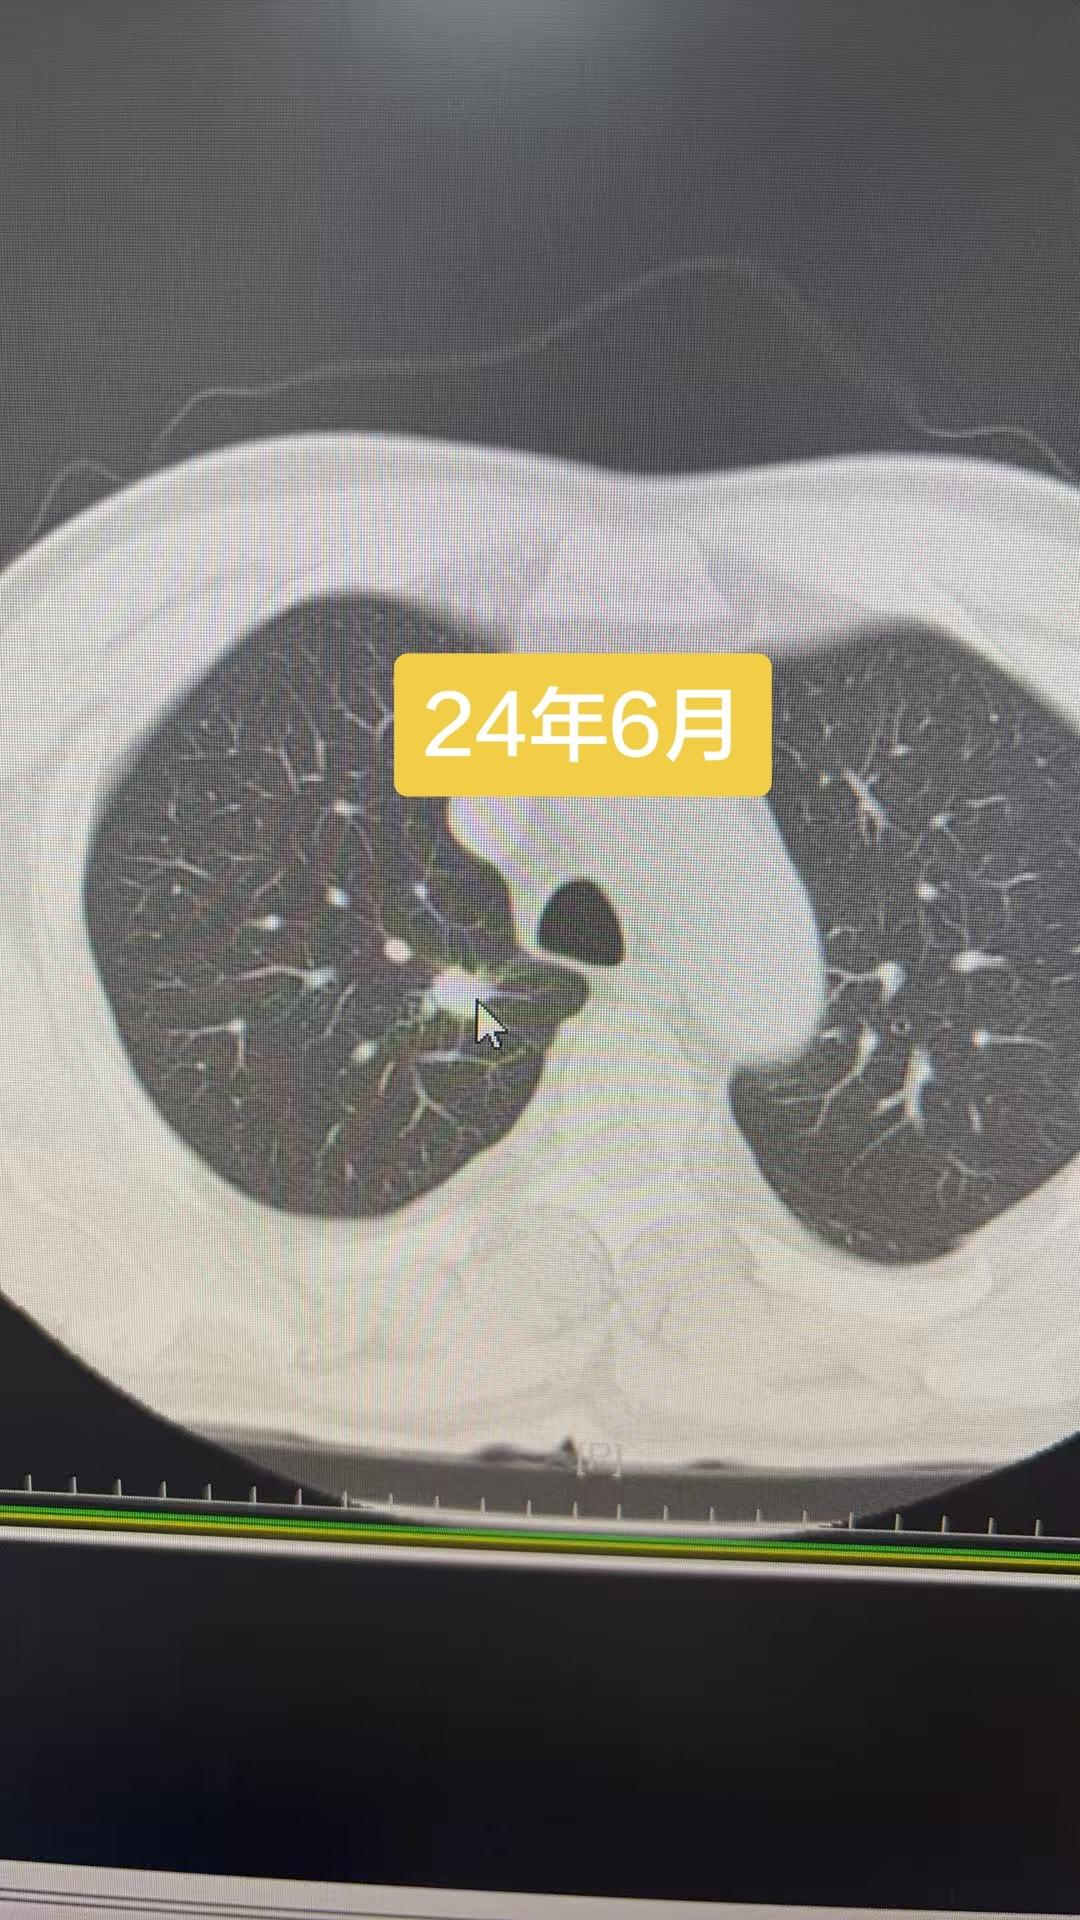

23年6月就发现的恶性结节,讳疾忌医,直接拖成晚期……猝于26年3月…...

23年6月就发现的恶性结节,讳疾忌医,直接拖成晚期……猝于26年3月……肺部结节虽然绝大多数是良性,持续增大的结节还是要重视,这个病人自己拖出大事……反面教材……